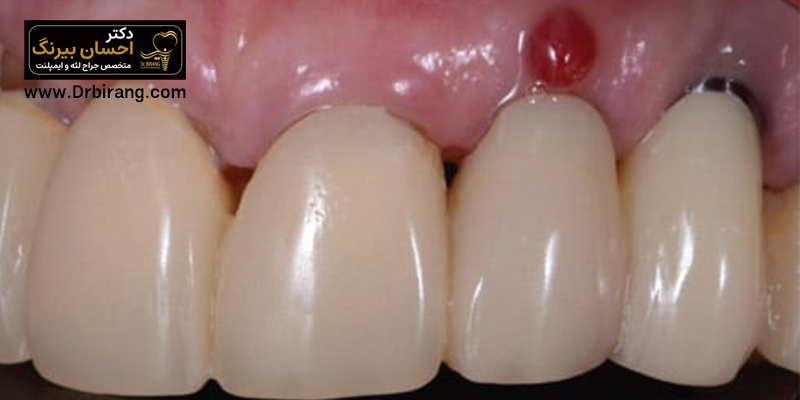

One of the common concerns among dental clients is to see an abnormal lump or lump on the gums. This bump, which is commonly called gum extra meat, may appear in different situations such as after surgery, tooth extraction, or even without any specific reason. If you have faced such a situation, you must have many questions in your mind; What is the cause of this condition, is it dangerous and how should it be treated? In this article from the website of Dr. Ehsan Birang, the best gum surgeon in Tehran, we answer all these questions.

In general, gum extra meat or gum hyperplasia is called excessive and abnormal growth of gum tissue. This complication is an unusual bump or lump that can appear anywhere in the mouth. This situation is different from extra gum (Gummy Smile); Extra gingiva is a natural condition in which a large part of the gum is visible when smiling and is usually not related to inflammation or disease. This distinction is very important and will help you diagnose the problem correctly.

Extra gum tissue after implant

Observation of extra gum tissue after implant can be caused by the body's reaction to a foreign object or an infection. If the dental prosthesis is not placed correctly on the implant or oral hygiene is not followed well after surgery, plaque and bacteria accumulate and cause inflammation and growth of extra tissue around the implant. This condition, which is called peri-implantitis, is very serious and must be checked by a dentist.